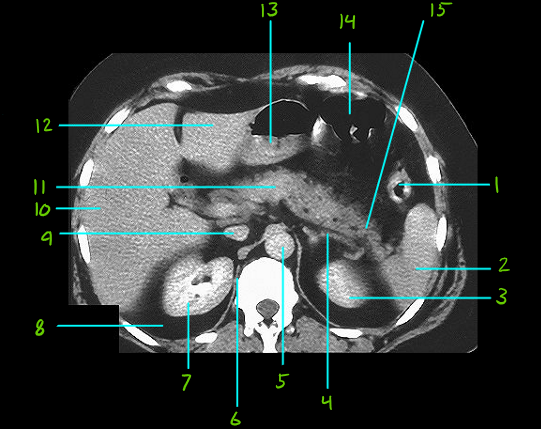

1

Q

What is #1

A

Descending colon

2

What is #2

Spleen

3

What is #3

Left kidney

4

What is #4

Left adrenal gland

5

What is #5

Aorta

6

What is #6

Diaphragm

7

What is #7

Right kidney

8

What is #8

Parirenal fat

9

What is #9

Inf. Vena cava

10

What is #10

Right lobe of liver

11

What is #11

Pancreas body

12

What is #12

Left lobe of liver

13

What is #13

Pyloric antrum

14

What is #14

Transverse colon